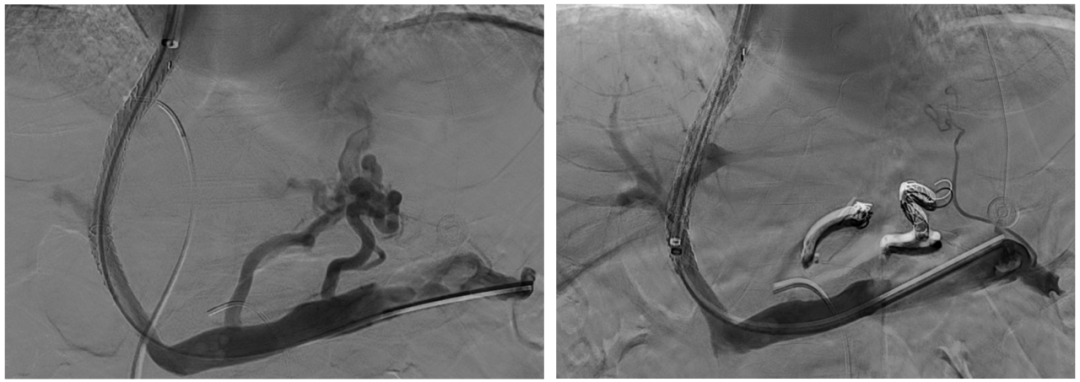

異常分流道栓塞后,再次行門靜脈造影,血流呈向肝狀態(tài),食管胃底曲張靜脈較前更顯著,微導管超選至曲張的胃冠狀靜脈,予以彈簧圈及25%生物膠栓塞,造影示曲張靜脈消失,肝內(nèi)門脈顯影較術(shù)前顯著改善

仔細評估術(shù)前CT可知,該患者的異常分流道的出口并不引流至腎上腺靜脈,故難以通過常規(guī)BRTO途徑栓塞,因而對于該患者團隊仔細評估后決定采用TIPS聯(lián)合異常分流道近端栓塞的方法。既往對于此類粗大分流道,無論是單純使用可控彈簧圈或是彈簧圈聯(lián)合組織膠水都存在栓塞效率或是安全性的不足,該患者使用血管塞封堵減緩血流后,在血管塞細密的網(wǎng)孔阻隔下能夠有效防止補充栓塞的組織膠逃逸,進而獲得良好的栓塞效果及效率。